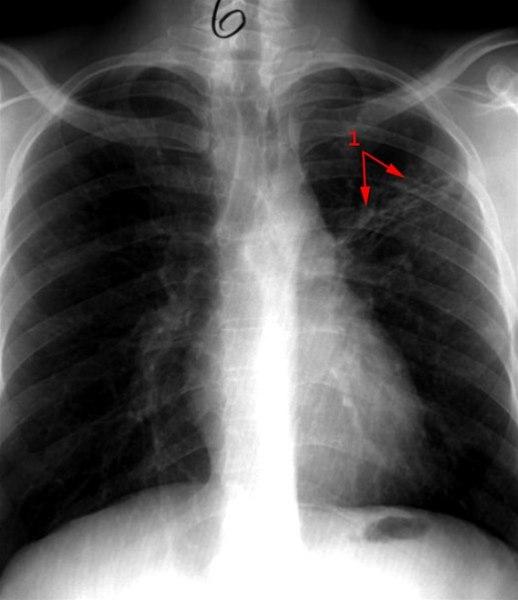

Primær tuberkulose - behandlet

Tilbakegang av forandringer (1) etter behandling med medikamenter